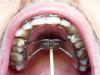

Киборг Опубликовано 10 октября, 2009 Поделиться Опубликовано 10 октября, 2009 (изменено) Надеюсь не обидится на меня Lea, я решил не создавать новой похожей темы, отпишусь здесь. 26 лет, год уже ношу брекеты, но не в этом суть, вобщем позавчера поставили мне расширитель на в.ч. Хотел узанть на сколько он должен прилегать к небу? Аппарат делали по слепку, но у меня в спокойном положении,при том что рот закрыт, расширитель лежит на языке, постоянно выделяются слюни, не могу нормально говорить, и от железки и от того что рот в слюнях. От расширителя до неба, ближе к передним зубам около 5 мм, сзади, другая сторона, до неба - 7мм. Не могу ни нормально глотать, ни сплюнуть, ни есть - все туда забивается. Если это все приплюсовать к брекетам с которыми я мучаюсь уже год, это вообще кошмар.Как быть с гигиеной с внутренней стороны в.ч. , если там эта железка?Выкладываю фото. Изменено 10 октября, 2009 пользователем Киборг Ссылка на комментарий

Orthodoc Опубликовано 12 октября, 2009 Поделиться Опубликовано 12 октября, 2009 Надеюсь не обидится на меня Lea, я решил не создавать новой похожей темы, отпишусь здесь. 26 лет, год уже ношу брекеты, но не в этом суть, вобщем позавчера поставили мне расширитель на в.ч. Хотел узанть на сколько он должен прилегать к небу? Аппарат делали по слепку, но у меня в спокойном положении,при том что рот закрыт, расширитель лежит на языке, постоянно выделяются слюни, не могу нормально говорить, и от железки и от того что рот в слюнях. От расширителя до неба, ближе к передним зубам около 5 мм, сзади, другая сторона, до неба - 7мм. Не могу ни нормально глотать, ни сплюнуть, ни есть - все туда забивается. Если это все приплюсовать к брекетам с которыми я мучаюсь уже год, это вообще кошмар.Как быть с гигиеной с внутренней стороны в.ч. , если там эта железка?Выкладываю фото. По снимку оценить качество постановки аппарата сложно, все неприятные ощущения, изложенные выше, должны уменьшиться к концу первой недели ношения. После приема пищи полощите рот, винт чистите зубной щеткой два раза в день. Ссылка на комментарий

Киборг Опубликовано 12 октября, 2009 Поделиться Опубликовано 12 октября, 2009 По снимку оценить качество постановки аппарата сложно, все неприятные ощущения, изложенные выше, должны уменьшиться к концу первой недели ношения. После приема пищи полощите рот, винт чистите зубной щеткой два раза в день. Ну по миллиметрам примерно можно сказать? На сколько он должен прилегать к небу? У меня там 5-7 мм получается, не ужели столько необходимо? Ссылка на комментарий

Orthodoc Опубликовано 15 октября, 2009 Поделиться Опубликовано 15 октября, 2009 Мда...Это зависит от формы неба, иногда винт при изготовлении аппарата не уложить на правильную глубину (в идеале, он должен отстоять на 3-4-мм от слизистой неба.) Ссылка на комментарий